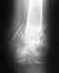

Помогите пожалуйста советом!! 26.11.2009.Поступил в травматологию с закрытым оскольчатым переломом костей левой голени в н/З со смещением.

Врачи говорили,что нужна операция,но после установки лангеты и спустя дней пять, мне наложили гипс и сказали, что все заживает и так. Подскажите, пожалуйста, возможно такое лечение с таким переломом или нужно предпринять более действенные способы/операция, установка пластины и т.д. Меня очень беспокоит этот вопрос, так как очень заинтересован в скорейшем выздоровлении и приступить к работе, которая кормит всю мою семью!!

Вообще - переломы голени лечатся в основном хирургически. Без снимка разговор беспредметный. Вы не указали, из какой Вы местности. Если недалеко от Екатеринбурга - можно приехать на очную консультацию (Московская, 12).